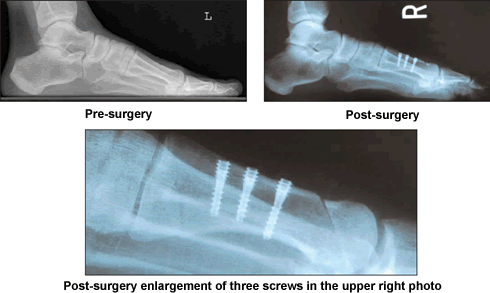

My daughter had moved to San Francisco, but my pain became unbearable. In August of 2004, I searched for information about my problem on The Baptist's web site. There I found Dr. Leavitt's credentials and read his articles on foot reconstruction. I telephoned The Baptist and asked to speak to Dr. Ken Leavitt. At his request, I had x-rays sent to him, then I talked to him twice more by phone from my home in Santos, Brazil.